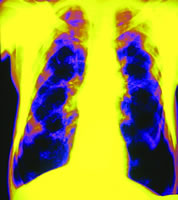

影像学技术的进步

COPD气流受限不但与小气道疾病(闭塞性细支气管炎)有关,还与肺实质结构的破坏(肺气肿)有关,在不同患者中两者所起的作用不同。薄层CT通过检测低附着区域可用于量化肺气肿,因此确立了CT在诊断肺气肿中的地位。然而,由于气流受限主要是小气道疾病所致,因此用FEV1来评价气流受限与用CT来评价肺气肿的严重程度之间并无很好的相关性。

近年来,有关CT技术的进展使其用于定量分析气道的异常成为可能。仿真支气管镜是基于CT技术评价气道腔内病变的一种新的无创性方法,其评价气道病变可达第八级支气管。理论上,薄层CT可以测量内径为1~2 mm的气道,因此CT可用于评价很多疾病的气道形态。

新影像技术软件通过曲线多维重建法来测量气道大小,结果表明气道管腔面积和气道壁面积均与FEV1占预计值的百分比相关,当气道越小时相关系数越大。

核医学扫描成像技术也用于评价COPD和肺气肿,及提供功能学影像。133Xe气体颗粒可用于肺通气显像,其中,单光子发射CT(SPECT)可用于评价小气道疾病及肺气肿,SPECT影像在评价小气道疾病(包括肺气肿在内)较高分辨率CT更有优势。

弥散加权超极化的3He磁共振成像被证实与肺功能,特别是肺一氧化碳弥散量(DLCO)相关。动态比较增强核磁影像可发现肺外周血管的异常,这些技术也可用于评价肺气肿。